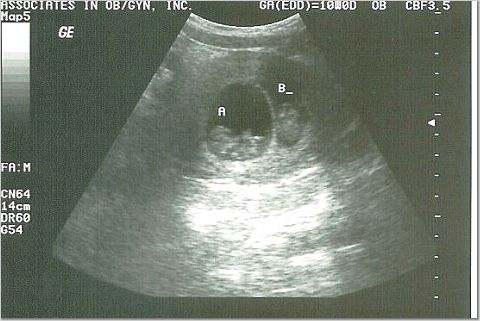

10 weeks - 3 centimeters

Heart rates 175 & 184